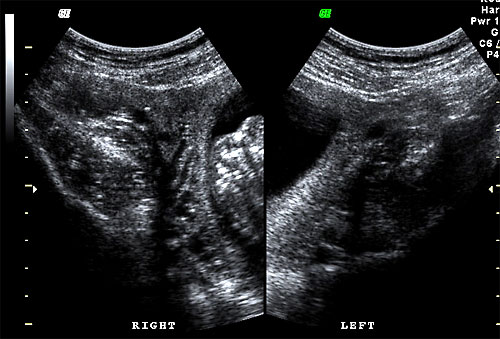

Normal right and left ovaries |